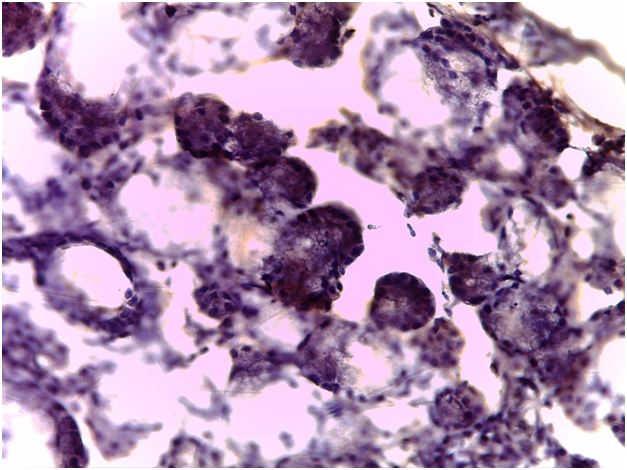

Immunohistochemical findings

As regards to immunohistochemistry (IHC), all cases of GBS have expressed focal positivity that ranged from moderate (++) to strong expression (++++) for CD68 (Figure 7) and CD16b (Figure 8). These cases have revealed a natively strong immunoreactivity for CD34 (Figure 9). The twelve cases showed negative expression for cathepsin-K. By contrast, the representative slides of both SS and normal mucosa did not display any significant immunoreactivity for the above mentioned immunohistochemical markers. To contrast, the main histological and immunohistological findings were compiled in Table 2.

Figure 8 Expression of CD16b in the salivary glandular tissue (original magnification 100x). Neutrophilic positivity is grossly expressed.